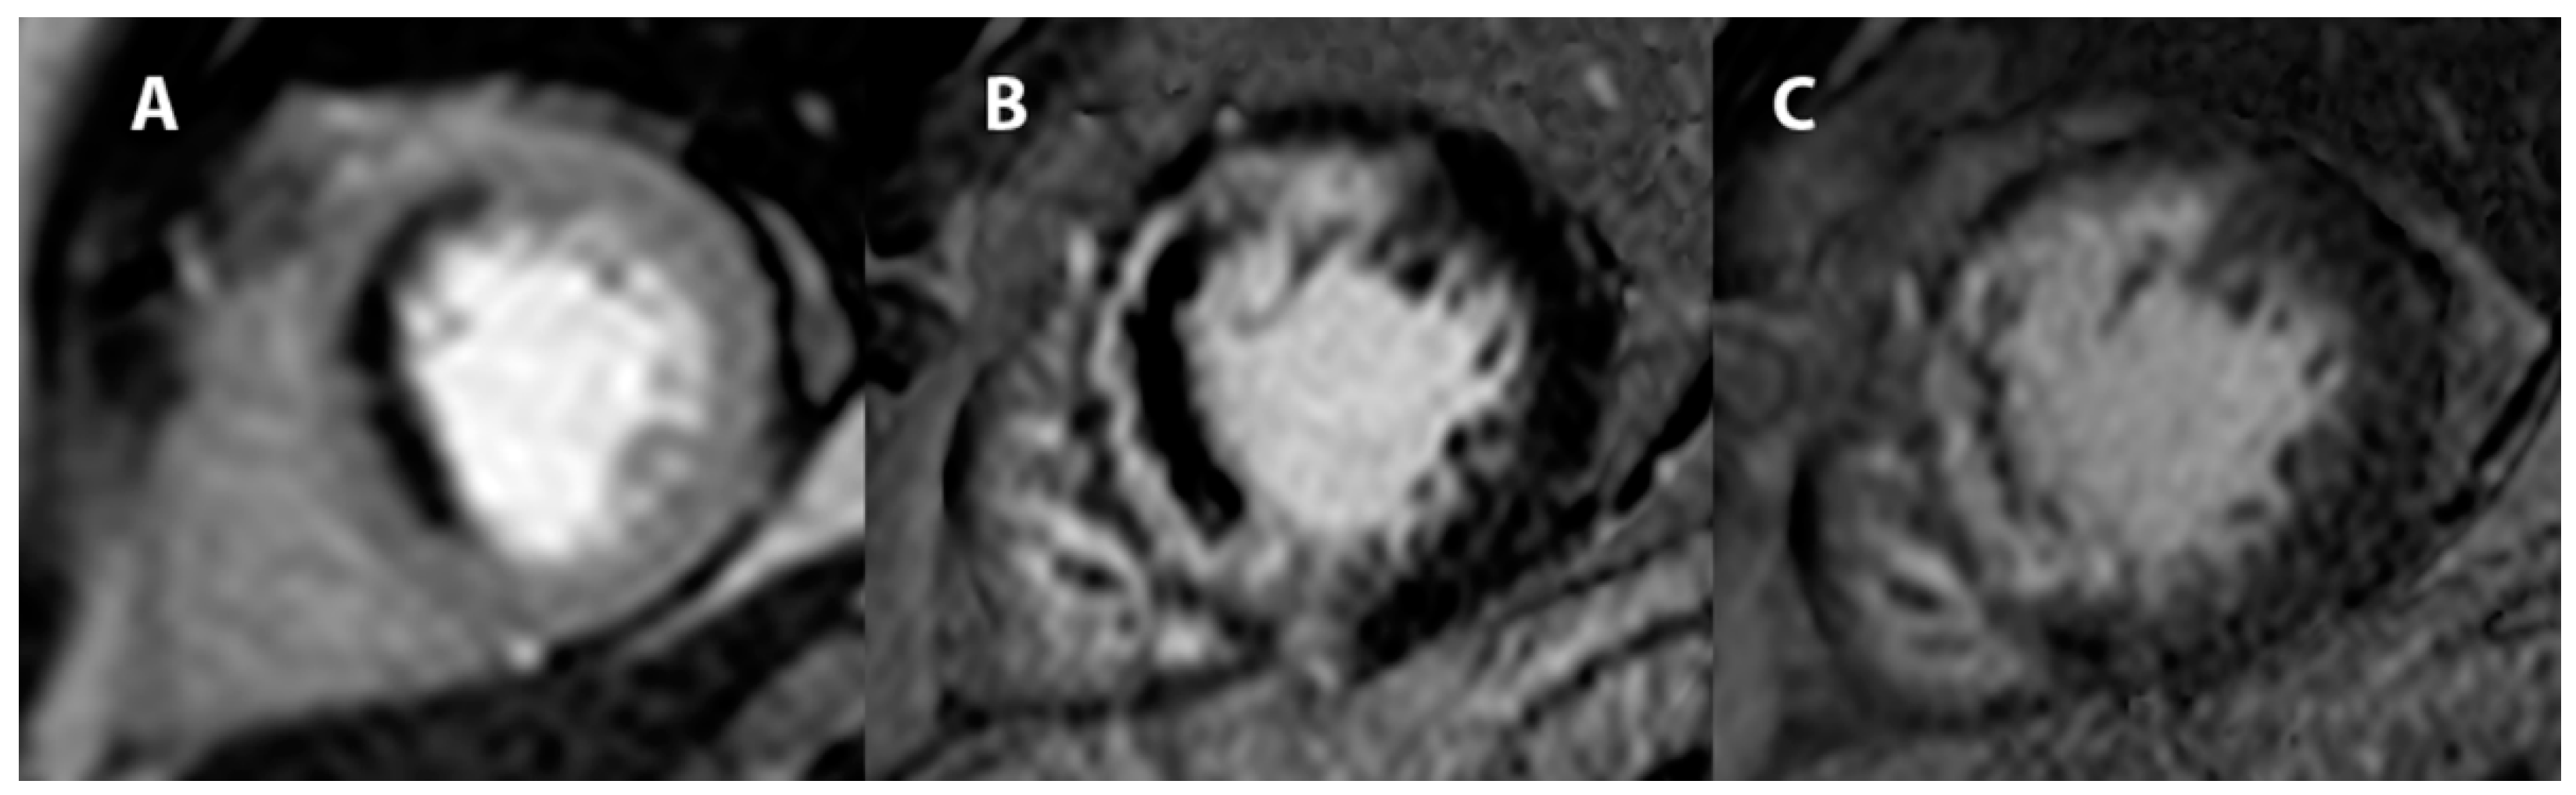

- Wu, K.C. CMR of microvascular obstruction and hemorrhage in myocardial infarction. J. Cardiovasc. Magn. Reson. 2012, 14, 68. [Google Scholar] [CrossRef]

- Abbas, A.; Matthews, G.H.; Brown, I.W.; Shambrook, J.S.; Peebles, C.R.; Harden, S.P. Cardiac MR assessment of microvascular obstruction. Br. J. Radiol. 2015, 88, 20140470. [Google Scholar] [CrossRef]

- Gatti, M.; Carisio, A.; D’Angelo, T.; Darvizeh, F.; Dell’Aversana, S.; Tore, D.; Centonze, M.; Faletti, R. Cardiovascular magnetic resonance in myocardial infarction with non-obstructive coronary arteries patients: A review. World J. Cardiol. 2020, 12, 248–261. [Google Scholar] [CrossRef]

- Sörensson, P.; Ekenbäck, C.; Lundin, M.; Agewall, S.; Brolin, E.B.; Caidahl, K.; Cederlund, K.; Collste, O.; Daniel, M.; Sensen, J.; et al. Early Comprehensive Cardiovascular Magnetic Resonance Imaging in Patients with Myocardial Infarction with Nonobstructive Coronary Arteries. JACC Cardiovasc. Imaging 2021, 14, 1774–1783. [Google Scholar] [CrossRef] [PubMed]